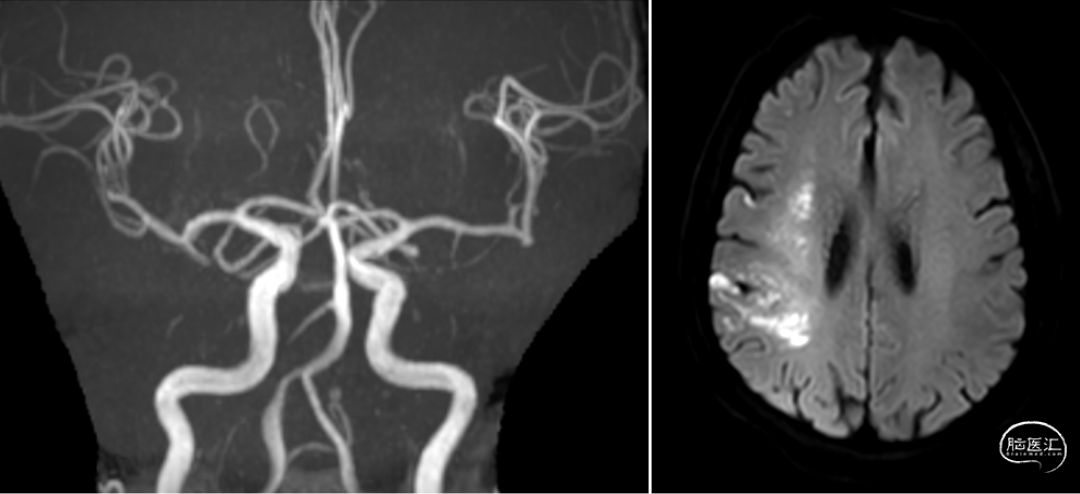

ASPECTS 9分

缺血体积124ml,梗死核心25ml

术前CTA提示右侧大脑中动脉M2段闭塞

右侧大脑中动脉上干闭塞(M2),影像评估机械取栓,抽拉结合,M2 位置较远,器械选择关键

术后复查血管通畅,少许梗塞